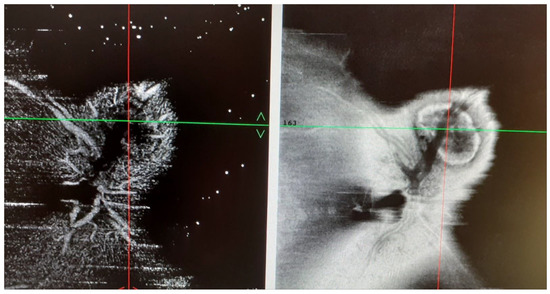

2. Case Presentation